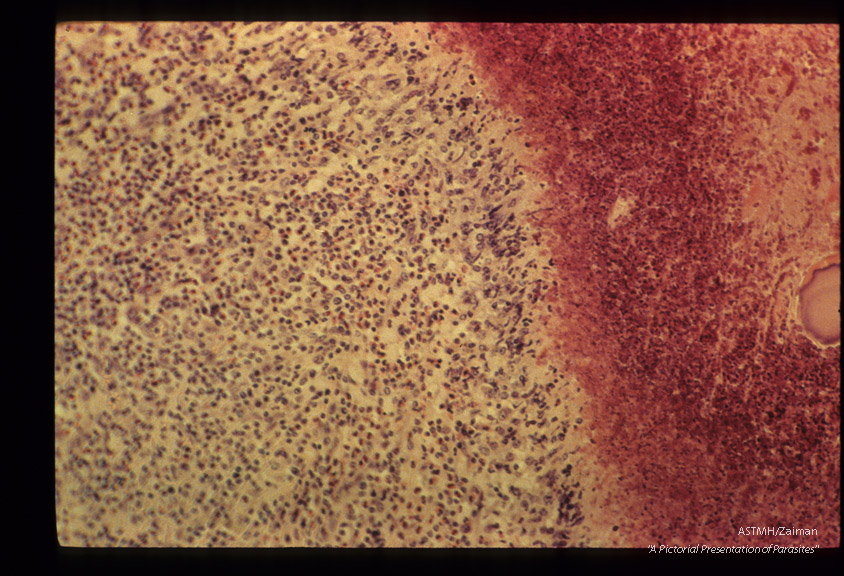

Traumatic hepatitis caused by migration of immature larvae. Junction of necrotic liver tissue and zone of cell reactions shown.

Fasciola hepatica

Description: Traumatic hepatitis caused by migration of immature larvae. Junction of necrotic liver tissue and zone of cell reactions shown.